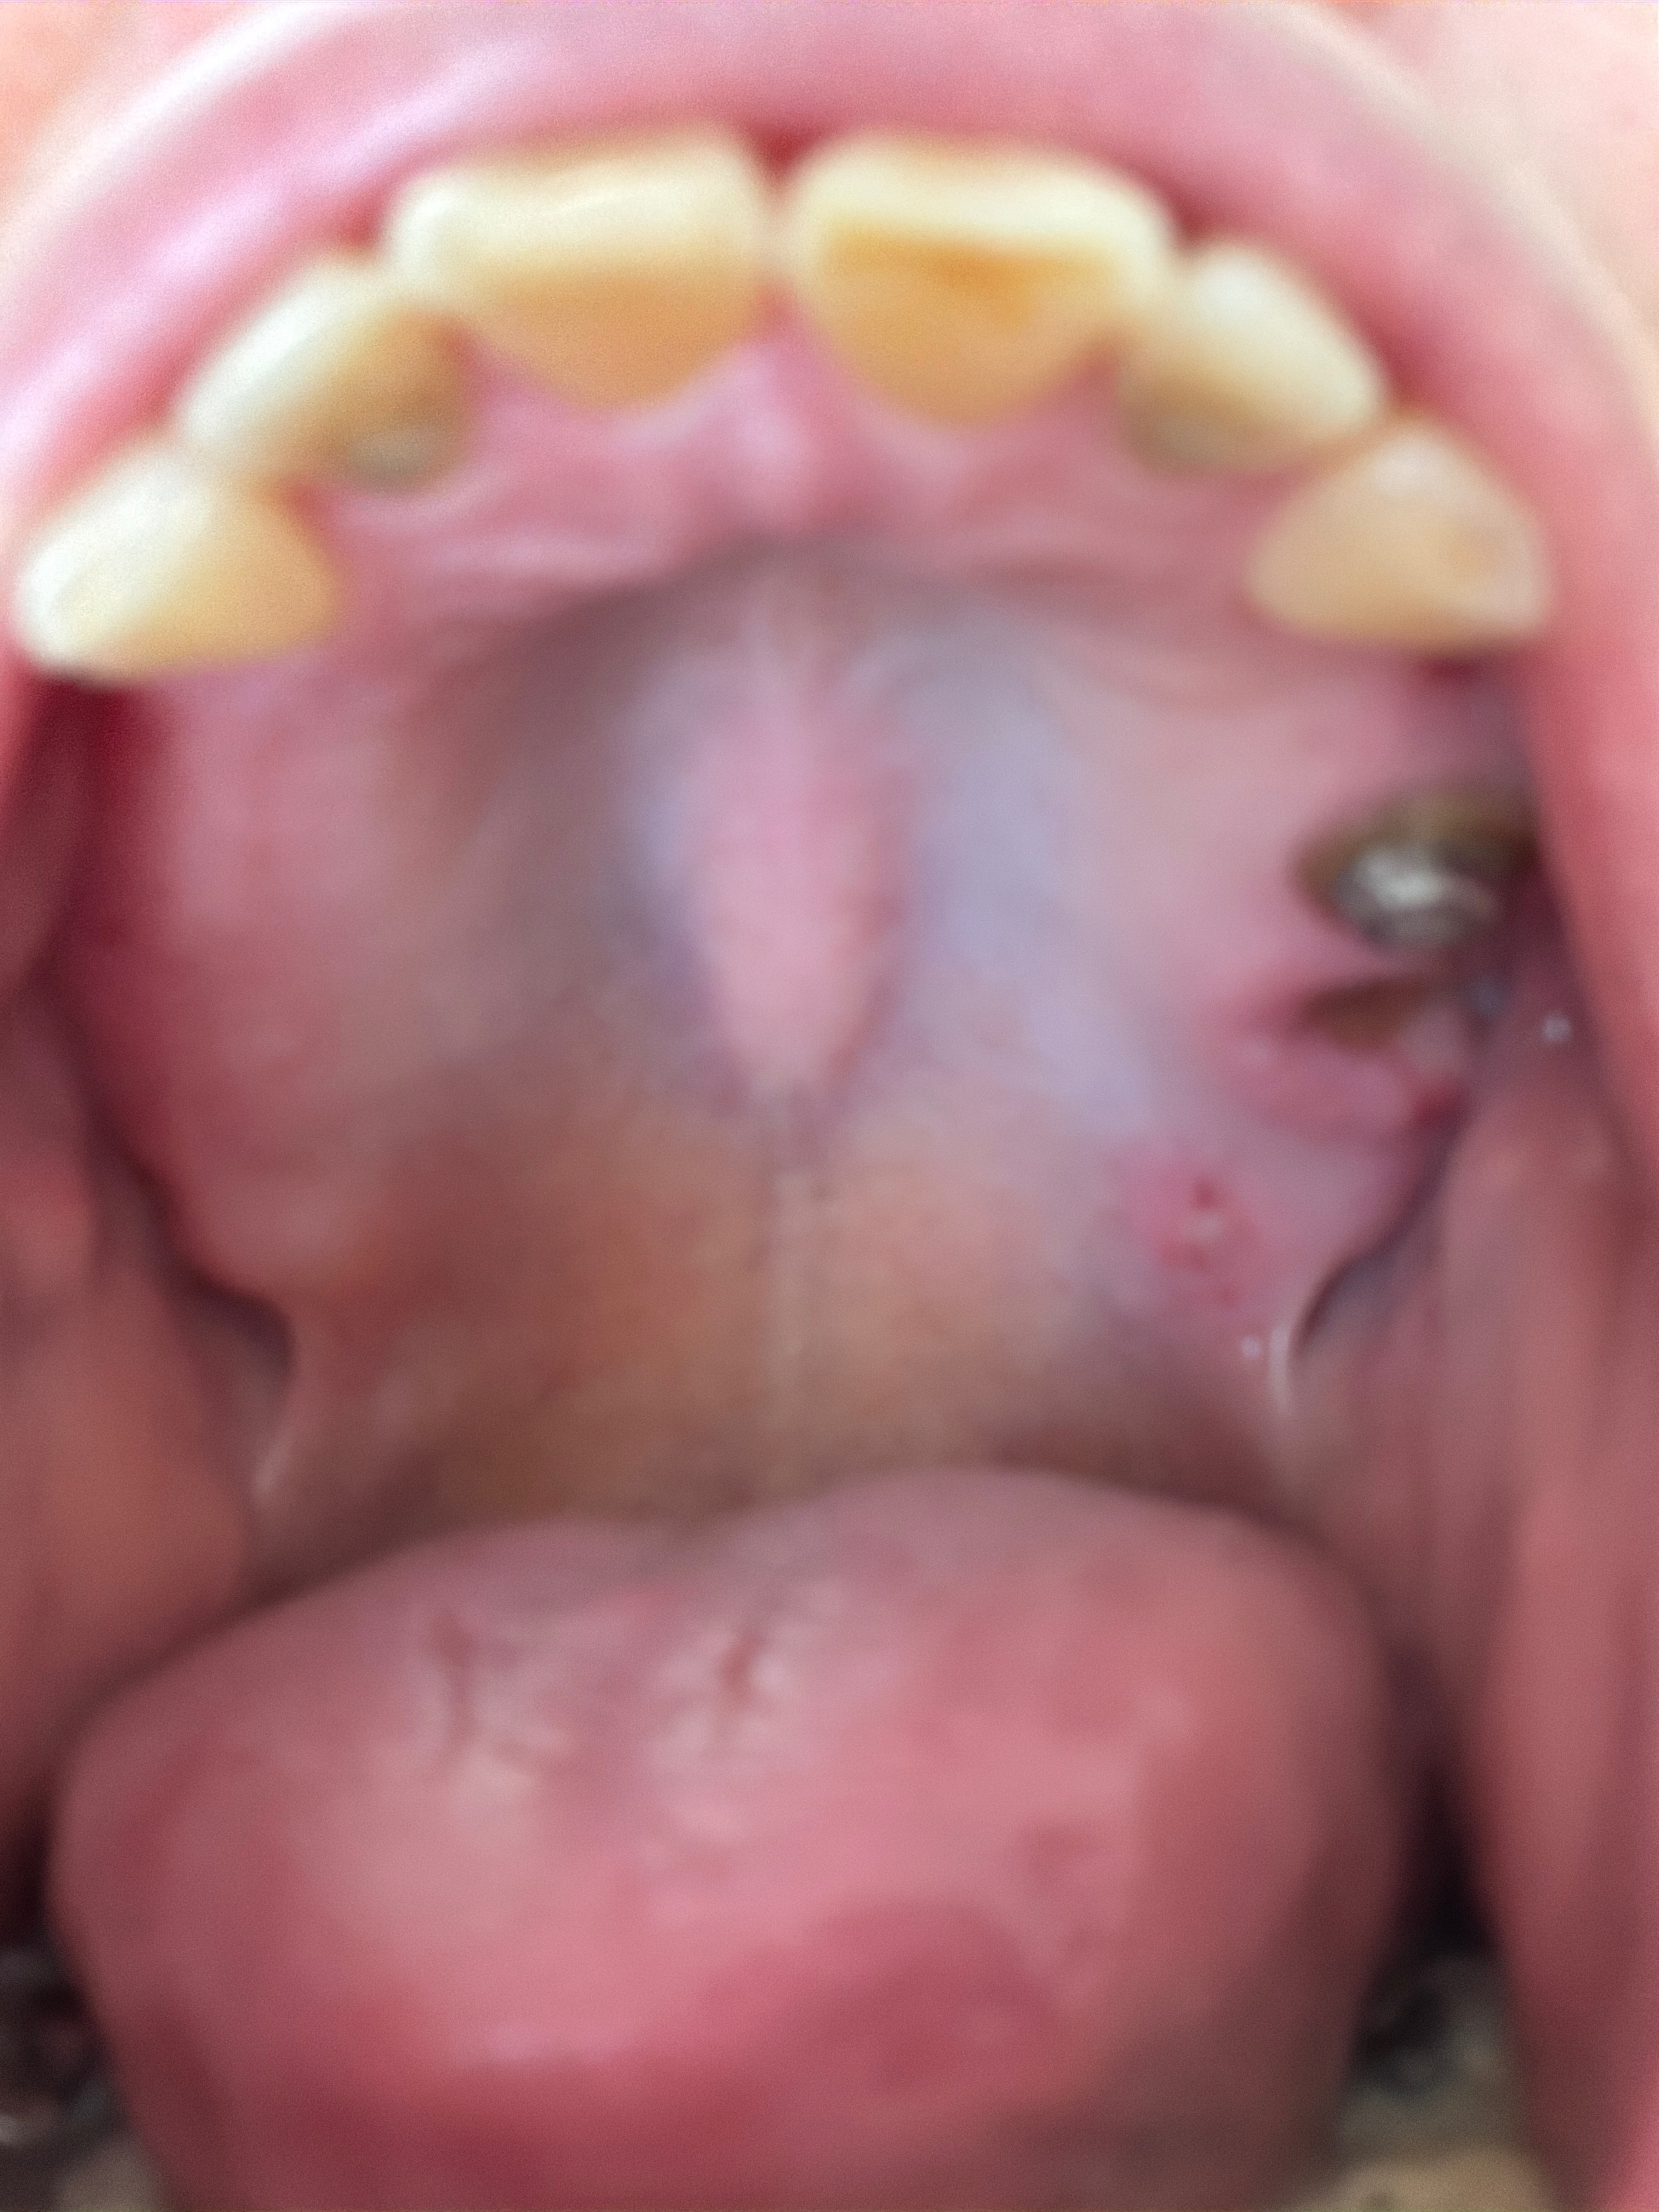

My name is Meghan, and I am almost three years sober. During my struggle with addiction, I neglected my health for a long time, and now I am facing the consequences. Recently, I found out that I have an infection in my left sinus that requires surgery next month. As part of the treatment, three of my teeth had to be pulled, leaving me with only six top teeth, all in the front. This has made it nearly impossible for me to chew anything, and I am struggling with both pain and embarrassment every day.